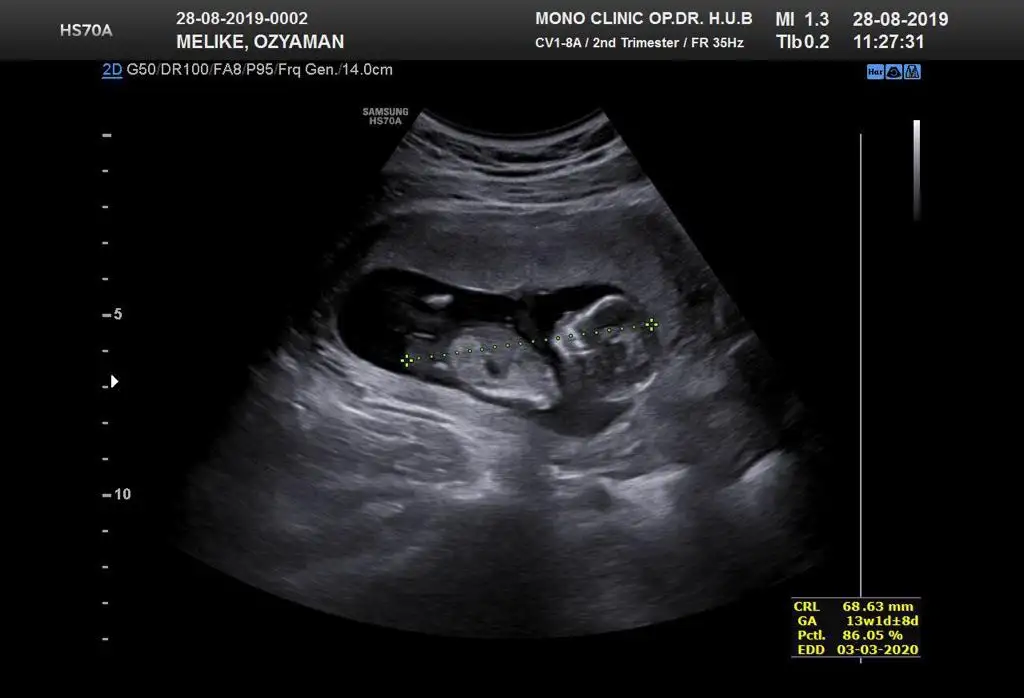

Kaç haftalık burda tam görünmüyor nub altı paralel geliyor yanılmıyorsam kız bu minnoşArkadaşlar merhaba ben de 13 haftalik hamileyim doktor yanilma payını düşünerek suan belirtmedi cinsiyetini yorumlarsaniz sevinirim. Tabi hic önemi yok cinsiyetin ama bir haftadir aşırı merak içindeyim:)) hepimize saglikla kucağına almayi nasip etsin

Canım teşekkürler öncelikle cevabin icin:) 13+3 o fotoğraftaKaç haftalık burda tam görünmüyor nub altı paralel geliyor yanılmıyorsam kız bu minnoş